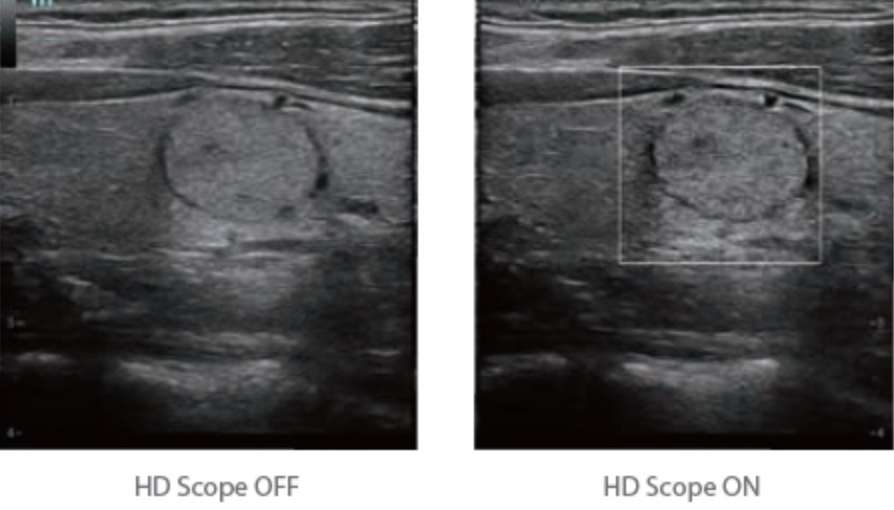

HD Scope: By processing channel data retrospectively, HD Scope enables tissue-specific enhancement with improved detailed information and image contrast on specific region of interest.